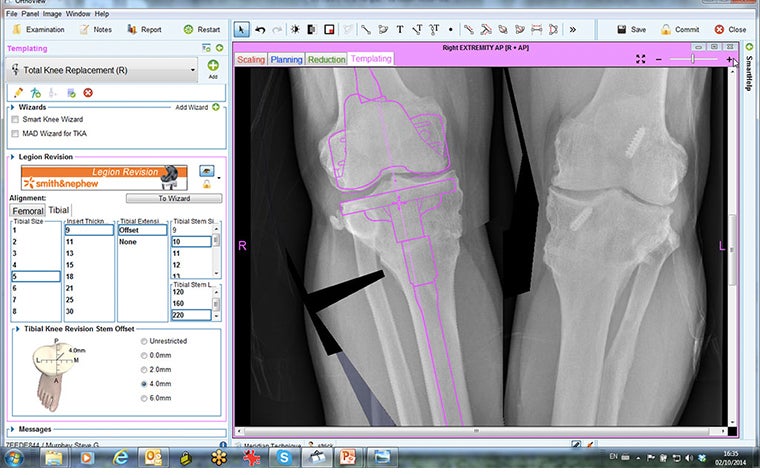

Having completed planning for the tibial osteotomy, the next phase of the plan was to use OrthoView’s ‘Add New Procedure’ feature to plan for the TKR.

A revision system, the Smith & Nephew Legion, was chosen since the optional offset stem would be used to help with fixation of the tibial osteotomy. Since the OrthoView digital orthopaedic template for the Smith & Nephew Legion behaves as a complete interconnected system, mimicking the behavior of the actual implant, templating for the necessary stem offset is possible.

The resulting preoperative plan provided not only the sizing of the components but also the positioning of the intra-articular cuts and insights into how these would subsequently affect ligament balancing.